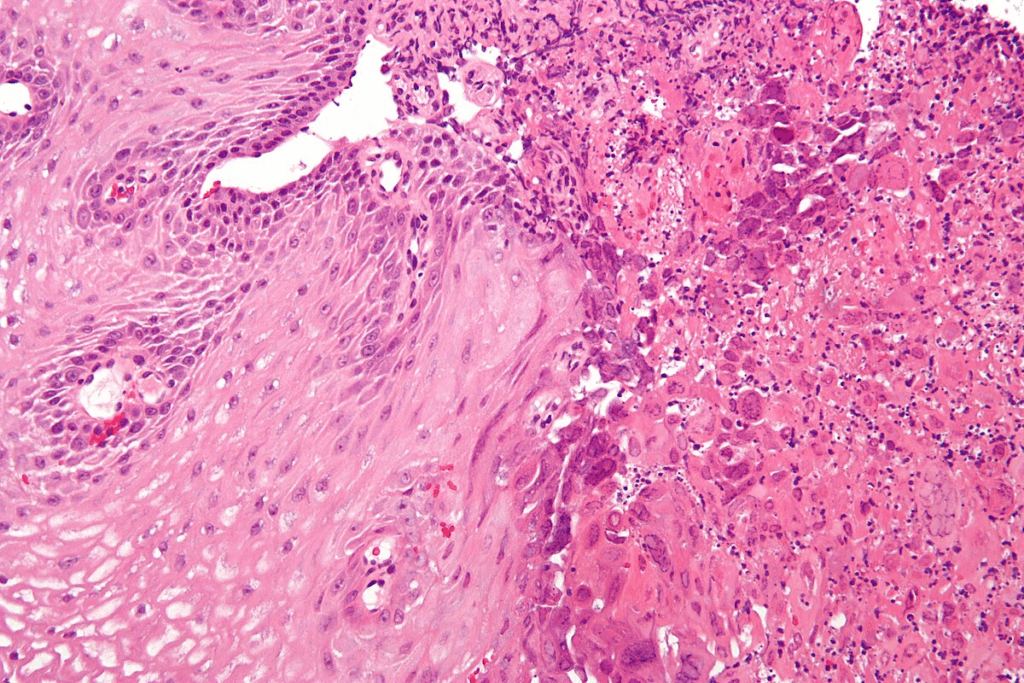

Definition and Types of Oral Cancer

Oral cancer happens in the mouth and throat. The most common type is squamous cell carcinoma. It starts from the lining of these areas. Other types like adenocarcinoma, melanoma, and lymphoma are less common.